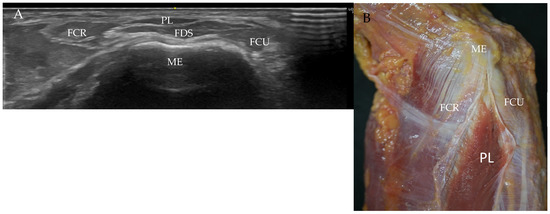

Palmaris Longus Muscle and Its Variations: Ultrasound, Anatomical and Histological Study with Clinical and Surgical Applications

Background/objective: The palmaris longus muscle is a variable and often inconsistent muscle in the anterior compartment of the forearm. This fusiform-shaped muscle originates at the medial epicondyle of the humerus bone following a long and narrow tendon that inserts at the palmar aponeurosis. [...] Read more.

Background/objective: The palmaris longus muscle is a variable and often inconsistent muscle in the anterior compartment of the forearm. This fusiform-shaped muscle originates at the medial epicondyle of the humerus bone following a long and narrow tendon that inserts at the palmar aponeurosis. That tendon is used in reconstructive surgery, and for this reason, detailed information from an ultrasound is used to detect the tendon and the possible variations in the muscle. The present study aimed to investigate the palmaris longus muscle and its variations through ultrasound, anatomical, and histological analysis with clinical and surgical applications. Methods: A total of 72 upper limbs from 33 females and 39 males, 32 right and 40 left, were evaluated in ultrasound, anatomical, and histological studies. The main objective was to prove the existence of the palmaris longus muscle and its variations, as well as to measure the tendon for surgical applications. Results: Ultrasound analysis showed that it is possible to determine the existence of the muscle (76.4%) and its variations (23.6%), as well as its absence (15.3%). The anatomical results proved the ultrasound results. The width of the tendon was between 0.4 and 0.38 mm. by ultrasound and anatomical analysis. Also, normal palmaris longus tendons were not a direct cause of compression of the median nerve. Conclusions: It is important to confirm the existence and possible variations in the palmaris longus muscle and tendon through ultrasound before surgical reconstruction and for clinical diagnostics. Full article